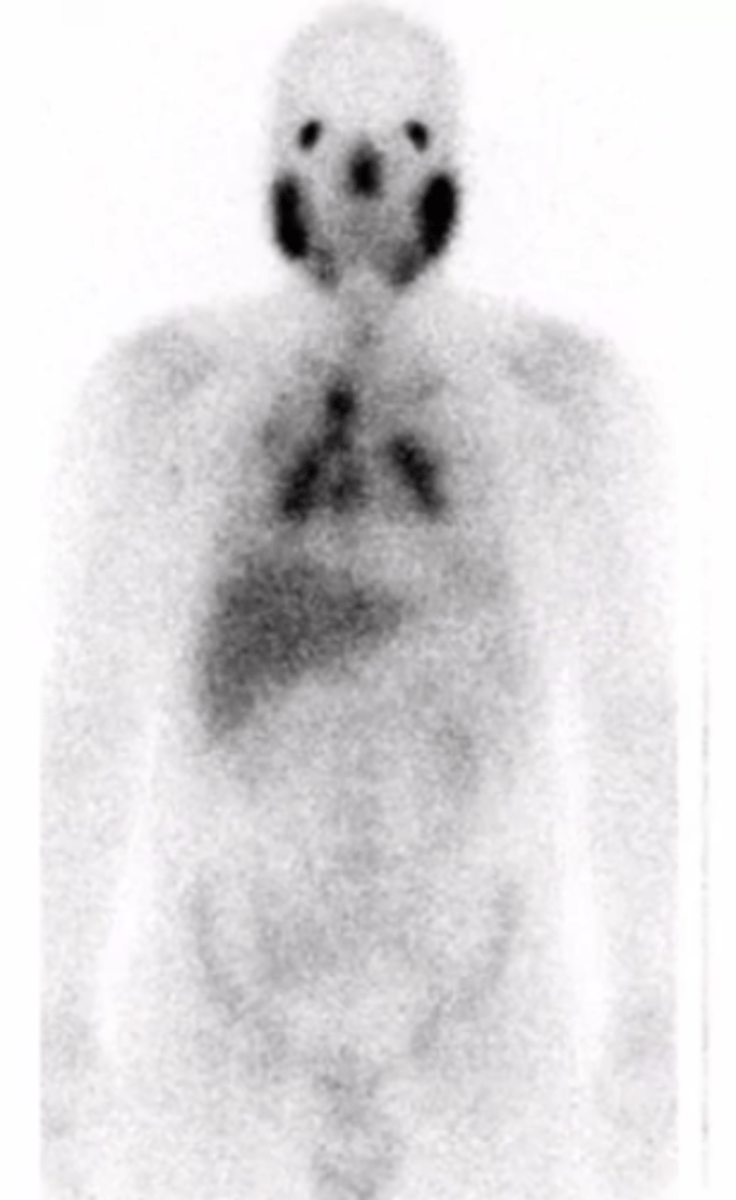

What does a PET scan show with sarcoidosis?

gallium uptake of the parotids or other regions for involvement

What is the "panda sign" in sarcoidosis?

uptake in the parotids

What is the "lambda sign" in sarcoidosis?

uptake in the chest